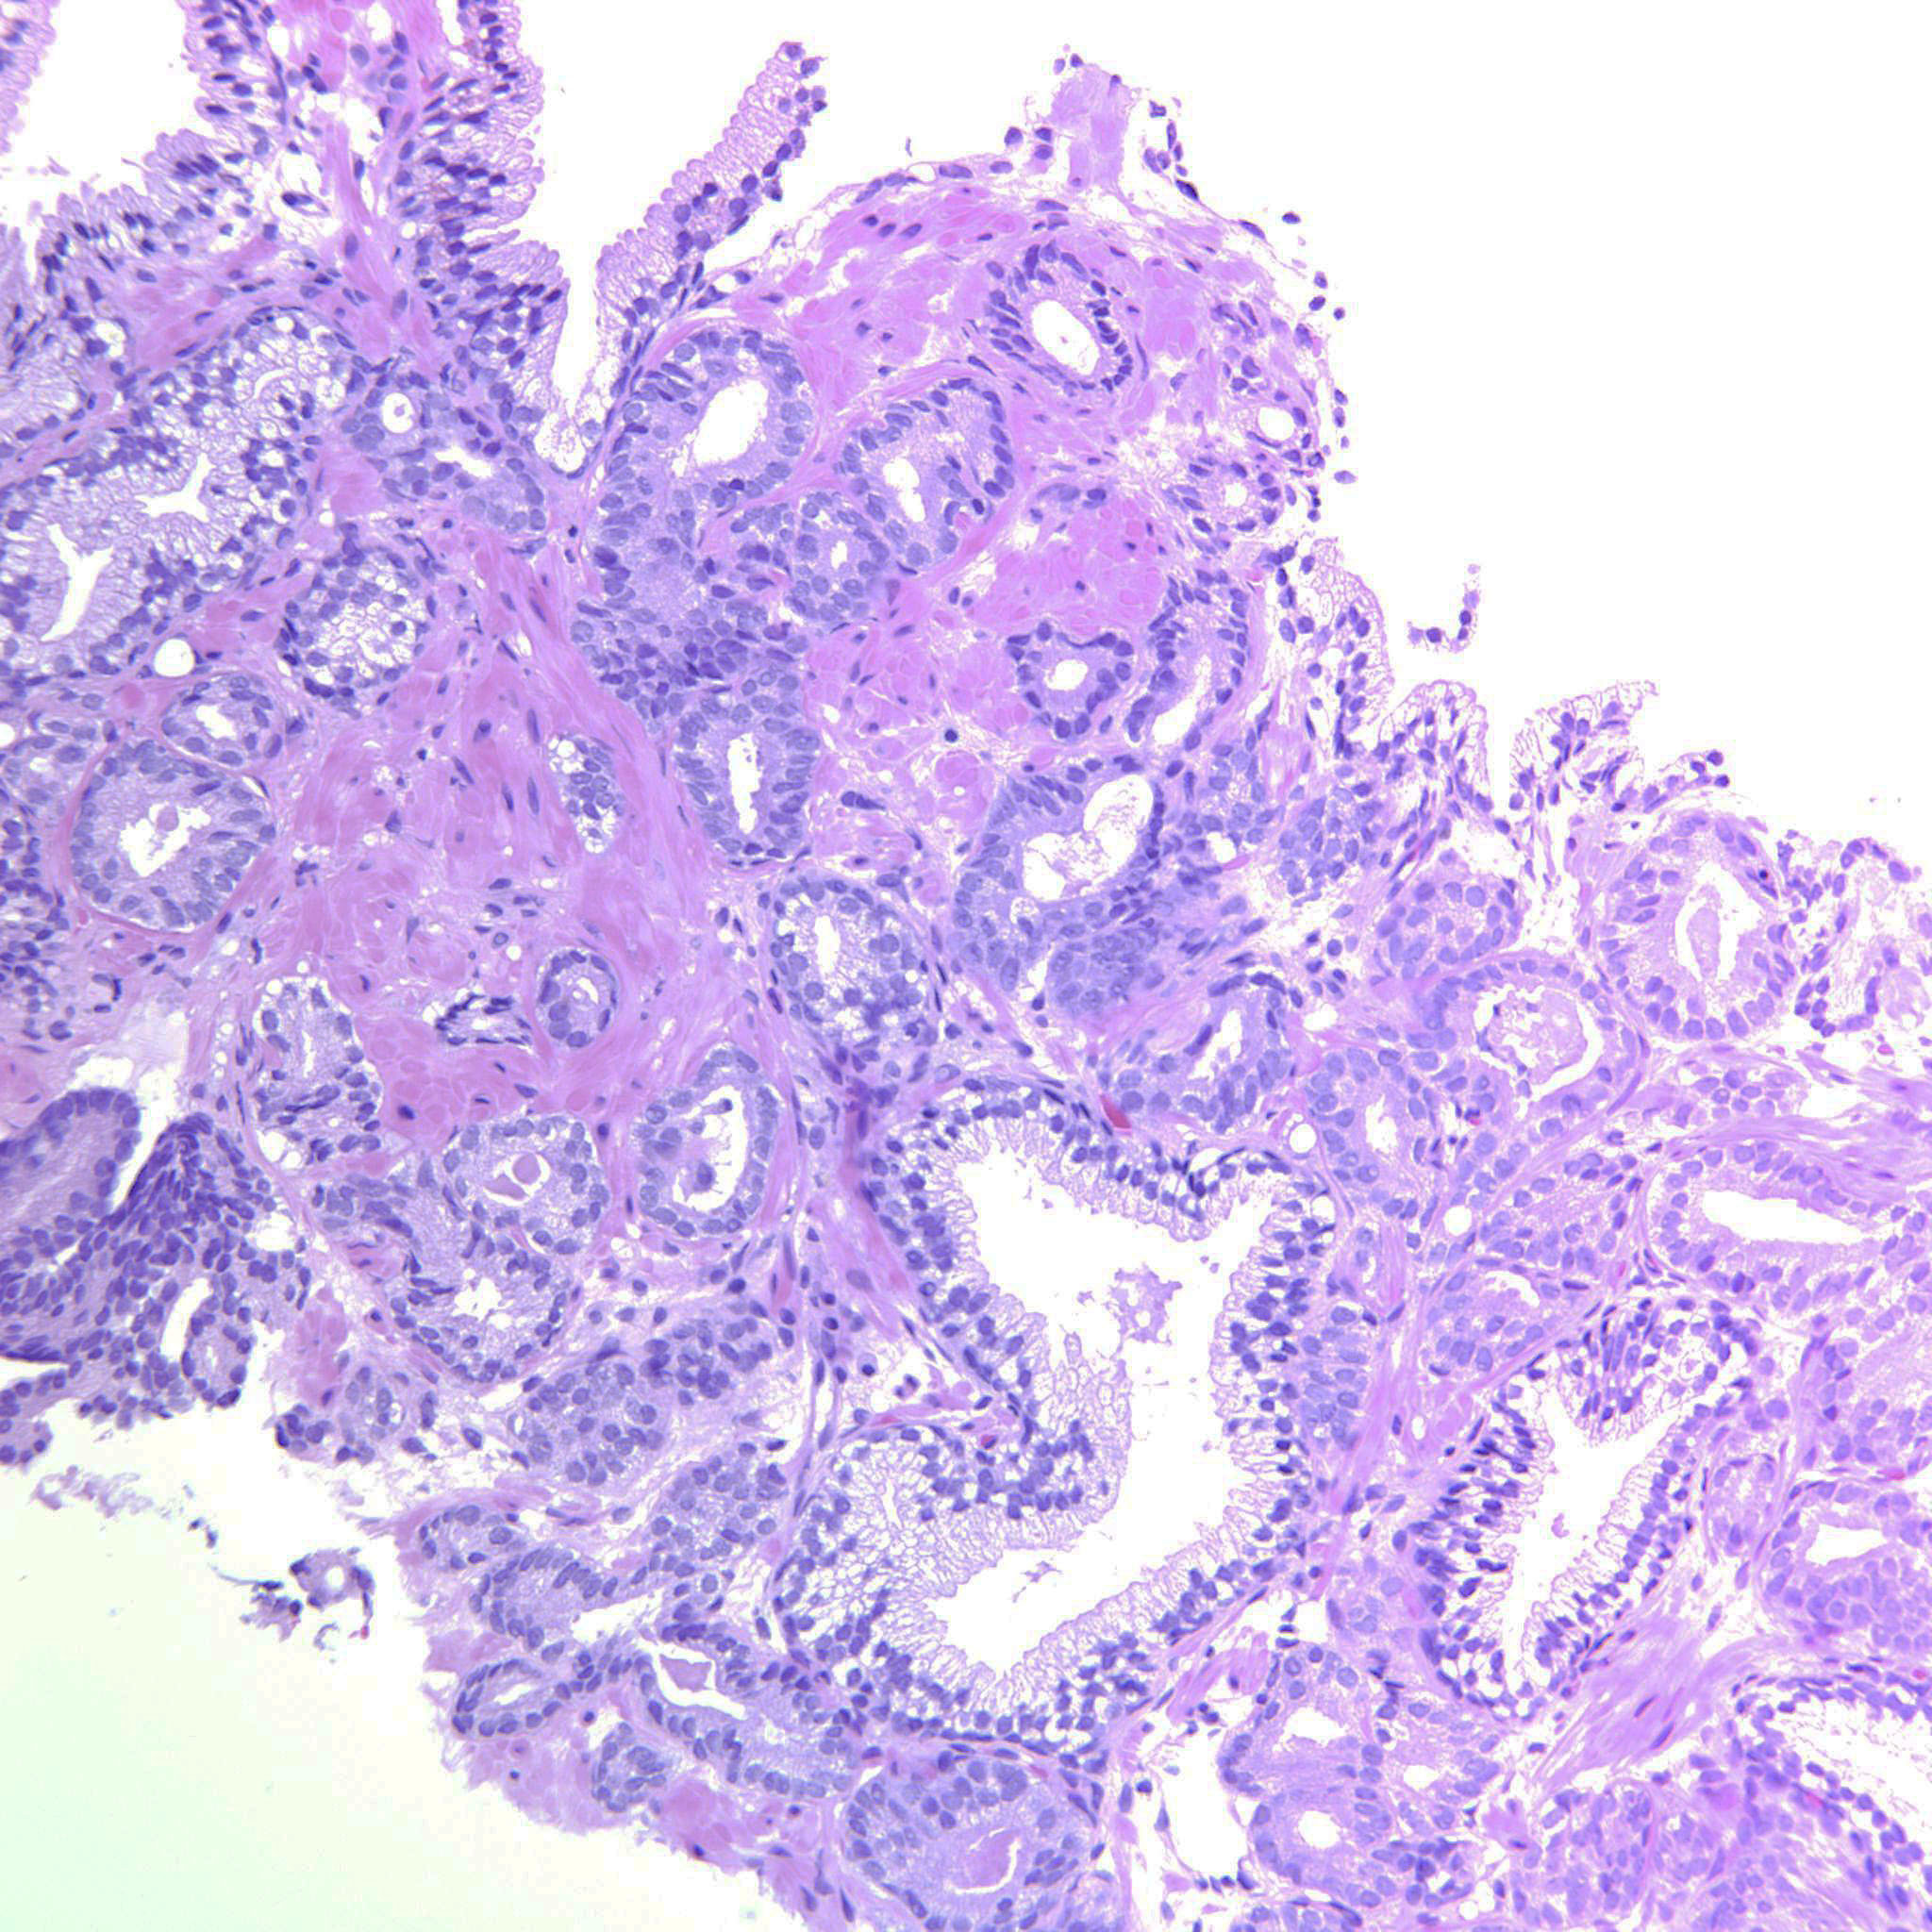

Prostate cancer grading

Case ID: 643